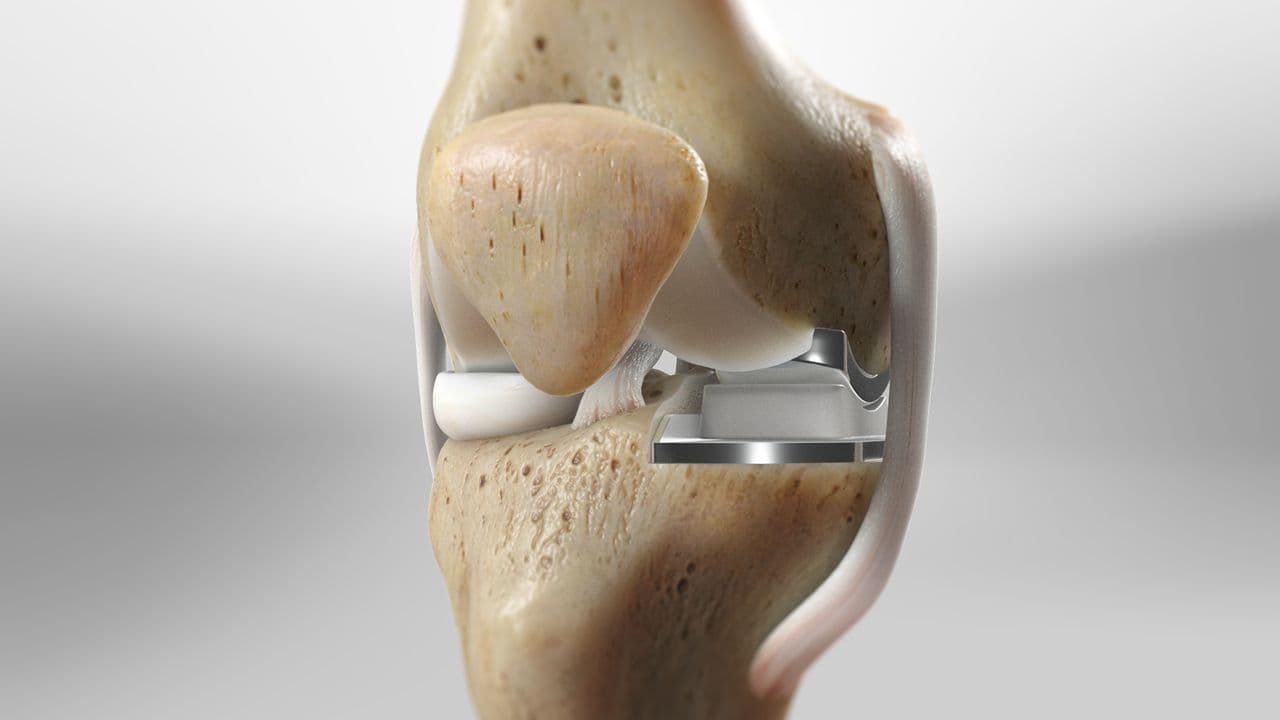

During a total knee replacement surgery, the damaged bone and cartilage are removed from the knee joint and replaced with artificial components. These components typically include a metal femoral component, a metal and plastic tibial component, and a plastic patellar component. The artificial parts are designed to mimic the natural movement of the knee, allowing for improved function and reduced pain. The surgery involves making an incision over the knee, removing the damaged tissue, and securing the new components to the bone using specialized cement or other fixation methods.

Partial and total knee replacements are surgical procedures designed to alleviate pain and restore function in patients with severe knee arthritis, but they differ significantly in their approach and scope. This procedure is less invasive, preserving more of the patient's natural knee structures, including the ligaments. In contrast, total knee replacement involves replacing all three compartments of the knee: the medial, lateral, and patellofemoral (front) compartments. This procedure is recommended for patients with widespread arthritis affecting the entire knee joint. During the surgery, the damaged bone and cartilage are removed and replaced with metal and plastic components designed to mimic the natural movement of the knee.